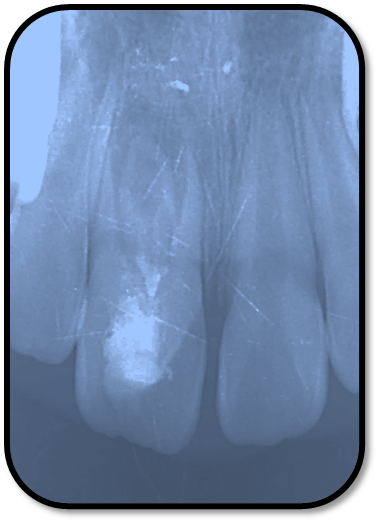

检查: 右上1牙冠略宽大,舌侧见粗大的畸形舌尖,叩痛(++),松Ⅰ°,唇侧牙龈红肿前庭沟膨隆扪痛,挤压唇侧龈缘溢脓,冷热测无反应,右侧上下1侧方颌,正中颌颌创伤。 X线:右上1发育7-8期,根管平行状,根尖孔宽大,约5-6mm宽,根尖周低密度影。髓腔根管宽大内见倒置牙影像,倒置牙可见髓腔。 余牙未见异常 6均已萌出建颌

随访复查: 治疗完成后1个月复查:右上1临床检查无阳性体征,叩痛(—),冷测无反应,无松动,牙龈无红肿,充填物完好,牙冠略有变色, X线检查:牙根根继续发育,可见钙化影像形成,如图示 治疗完成后7个月复查:临床检查无阳性体征,充填物完好,牙冠变色局部发黑,叩痛(—),冷测无反应,无松动,牙龈无红肿,临床及 X线检查:牙根继续发育,如图示 治疗完成后17个月复查:临床检查无阳性体征,充填物完好,牙冠变色局部发黑,叩痛(—),冷测无反应,无松动,牙龈无红肿。X线:牙根继续发育,根尖孔已近闭合。如图。 讨论: